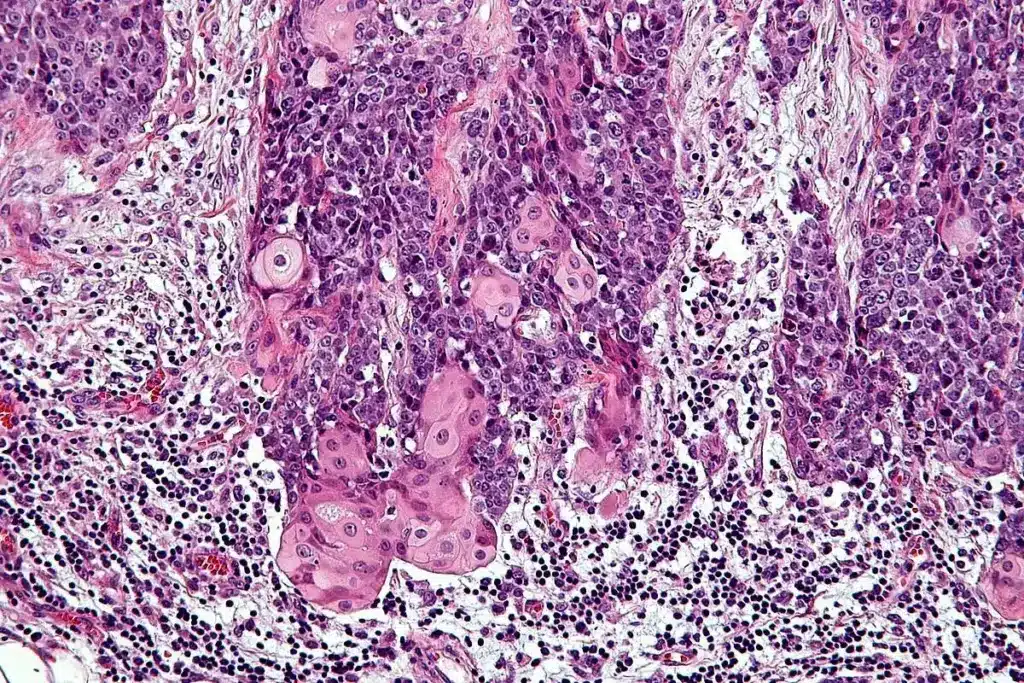

Skin Cancer Pictures: A Visual Guide

A visual guide to skin cancer helps people spot cancerous spots early. This is key for catching skin cancer before it’s too late.

Melanoma Images and Color Variations

Melanoma, the deadliest skin cancer, comes in many colors and shapes. Knowing what melanoma looks like is vital for early detection. Asymmetry, irregular borders, and multiple colors are signs to watch for.

Melanoma can be dark brown to black, and sometimes pink, red, or white. These colors make it hard to spot, but knowing the signs helps.

Basal and Squamous Cell Carcinoma Pictures

Basal cell carcinoma (BCC) and squamous cell carcinoma (SCC) are common skin cancers. BCC looks like a small, shiny bump or a pink patch. SCC is a firm, red nodule or a scaly patch.

Images of BCC and SCC help people spot these cancers early. Look for translucent or pearly appearances in BCC, and rough or scaly textures in SCC.